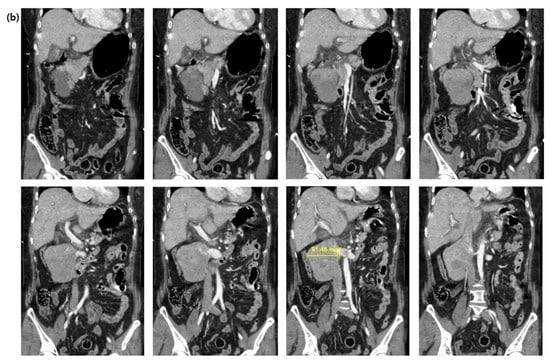

Figure 2.

(a) Computed tomography of the chest. Arrows indicate massive pulmonary embolisms. (b) Computed tomography of the brain. Green arrowheads indicate widely decreased gray matter density. Yellow arrow indicates hyperdense middle cerebral artery sign.

A 58-year-old woman with an unremarkable medical history visited the emergency department (ED) for worsening dizziness and dyspnea, noted one day before. The patient was alert and had normal peripheral oxygen saturation (SpO2) when the paramedics arrived. However, her mental state and oxygen saturation level declined during transport to the hospital. She had an SpO2 of 83% despite receiving 100% oxygen supplementation through a face mask with a reserve bag. The blood pressure was not measured due to a weak pulse. The patient was drowsy upon arrival at the ED. Cardiac arrest with pulseless electrical activity occurred after five minutes, and spontaneous circulation was restored after two minutes of cardiopulmonary resuscitation. A computed tomography (CT) of the brain, chest, and abdomen–pelvis (AP) was taken two hours after arrival. The AP-CT revealed an 8 × 11 cm saccular aneurysm involving the left and right renal veins at the infrahepatic level of the IVC (Figure 1). The chest CT revealed massive pulmonary embolisms involving both distal main pulmonary arteries (Figure 2a). A hyperdense middle cerebral artery (MCA) sign indicating thrombosis of the M1 MCA segment and widely decreased gray matter densities in the left hemisphere and right frontal lobe were detected on the brain CT (Figure 2b) [5]. A tissue plasminogen activator was administered two and a half hours after arrival, and the patient was admitted to the intensive care unit. The patient developed a seizure; therefore, a follow-up brain CT was performed after six hours. This showed a broad infarcted area involving most of the cerebrum, except for the thalamus and right occipital lobe. An electroencephalogram taken two days after admission suggested the possibility of brain death, and a bedside transthoracic echocardiography performed on the fourth day of hospitalization showed an enlarged RV with reduced RV systolic function. The patient’s family decided against a further evaluation or advanced treatment; therefore, the patient was conservatively managed at this point. Normal blood pressure was not achieved despite administering high-dose inotropic agents during the seventh day of hospitalization, and the patient died on the eleventh day of hospitalization.